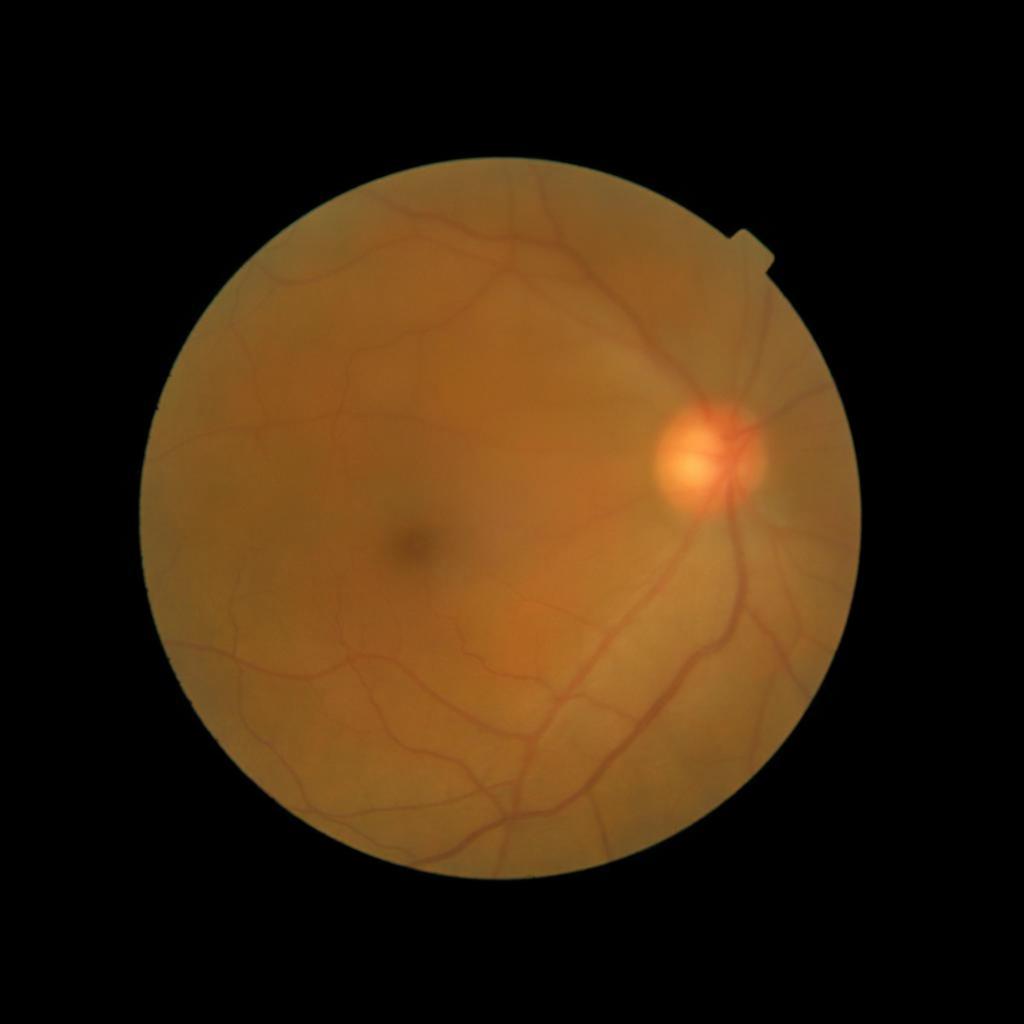

Diffusion models have recently gained significant traction due to their ability to generate high-fidelity and diverse images and videos conditioned on text prompts. In medicine, this application promises to address the critical challenge of data scarcity, a consequence of barriers in data sharing, stringent patient privacy regulations, and disparities in patient population and demographics. By generating realistic and varying medical 2D and 3D images, these models offer a rich, privacy-respecting resource for algorithmic training and research. To this end, we introduce MediSyn, a pair of instruction-tuned text-guided latent diffusion models with the ability to generate high-fidelity and diverse medical 2D and 3D images across specialties and modalities. Through established metrics, we show significant improvement in broad medical image and video synthesis guided by text prompts.

In this work, we focus on the ability of LDMs to generate novel datasets to overcome class imbalances traditionally associated with medical data, and potentially reduce the need for manual annotation of medical 2D and 3D data. We present MediSyn, a pair of text-guided latent diffusion models for broad medical 2D and 3D modality synthesis. To overcome the scarcity of labelled medical data, we leverage a vast corpus of more than 5 million image-caption pairs and 100,000 video-caption pairs collected from the public domain across numerous medical specialties, and integrate comprehensive natural language annotations to develop a pair of versatile diffusion models for the medical domain.

We assembled a set of 5,785,333 medical image-caption pairs, covering 8 specialties and 9 imaging modalities, to train Medisyn’s 2D model. We reserved an additional 1000 image-caption pairs (125 pairs from each specialty) for model evaluation.

| Ophthalmology | 174,246 |

Our findings demonstrate Medisyn’s remarkable ability to generate high-fidelity and diverse medical images, image sequences and volumetric scans across various medical subspecialties and imaging modalities. Other medical text-driven diffusion models, such as TauPETGen [42] for tau PET images and GenerateCT [43] for chest CT volumes, have proven successful in generating high-quality images that accurately depict anatomical features and clinical conditions. However, these models are constrained to a single imaging modality and anatomical region, thereby restricting their applicability. Moreover, they were trained on relatively small datasets sourced from a limited number of institutions, which could lead to more biased outputs. In contrast, Medisyn, having been trained on one of the largest publicly accessible medical image and video datasets to date, is equipped to synthesize data that cover numerous medical disciplines, population groups, and disease states. Leveraging our two models, we can synthesize new medical datasets as well as augment existing ones, potentially improving a wide array of medical machine learning tools, both general and specialized. Additionally, our models can minimize the need to repeatedly fine-tune on specific datasets for generating different imaging modalities, thus reducing computational costs for academic labs.